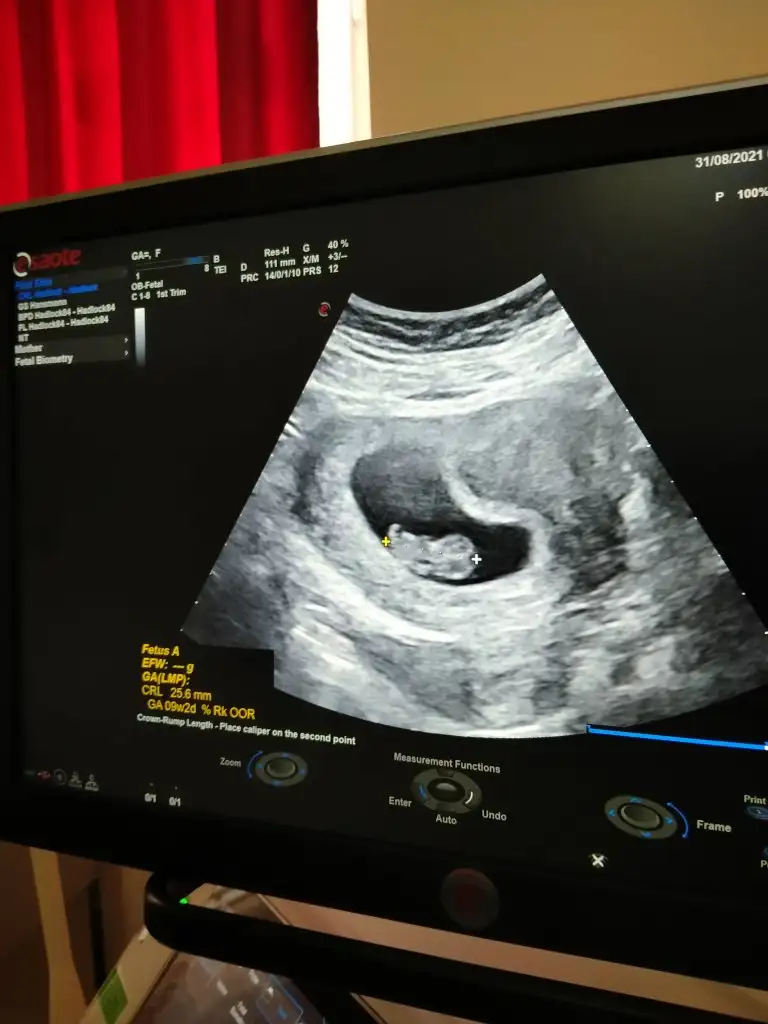

Ramzi teorisine göre cinsiyet tahmini yapacagim ilk ultrasyon resminizi atin bakiyim. Eger cinsiyetiniz belliyse hic söylemeeyin bakalm dogru tahmin edebilecekmiyim daha dogrusu ramzi teorisi hakli cikacak mi?

10 haftalık

Ramzi teorisine göre;

Teoriye göre, kromozomların farklı yöne gitmesi ile plasentanın hangi durumda olduğu belirlenir. Yani plasentanın bulunduğu konum bebeğin cinsiyetini vermektedir. Plasenta rahmin sağında ise erkek, solunda ise kız bebek olacağı anlamına gelir.